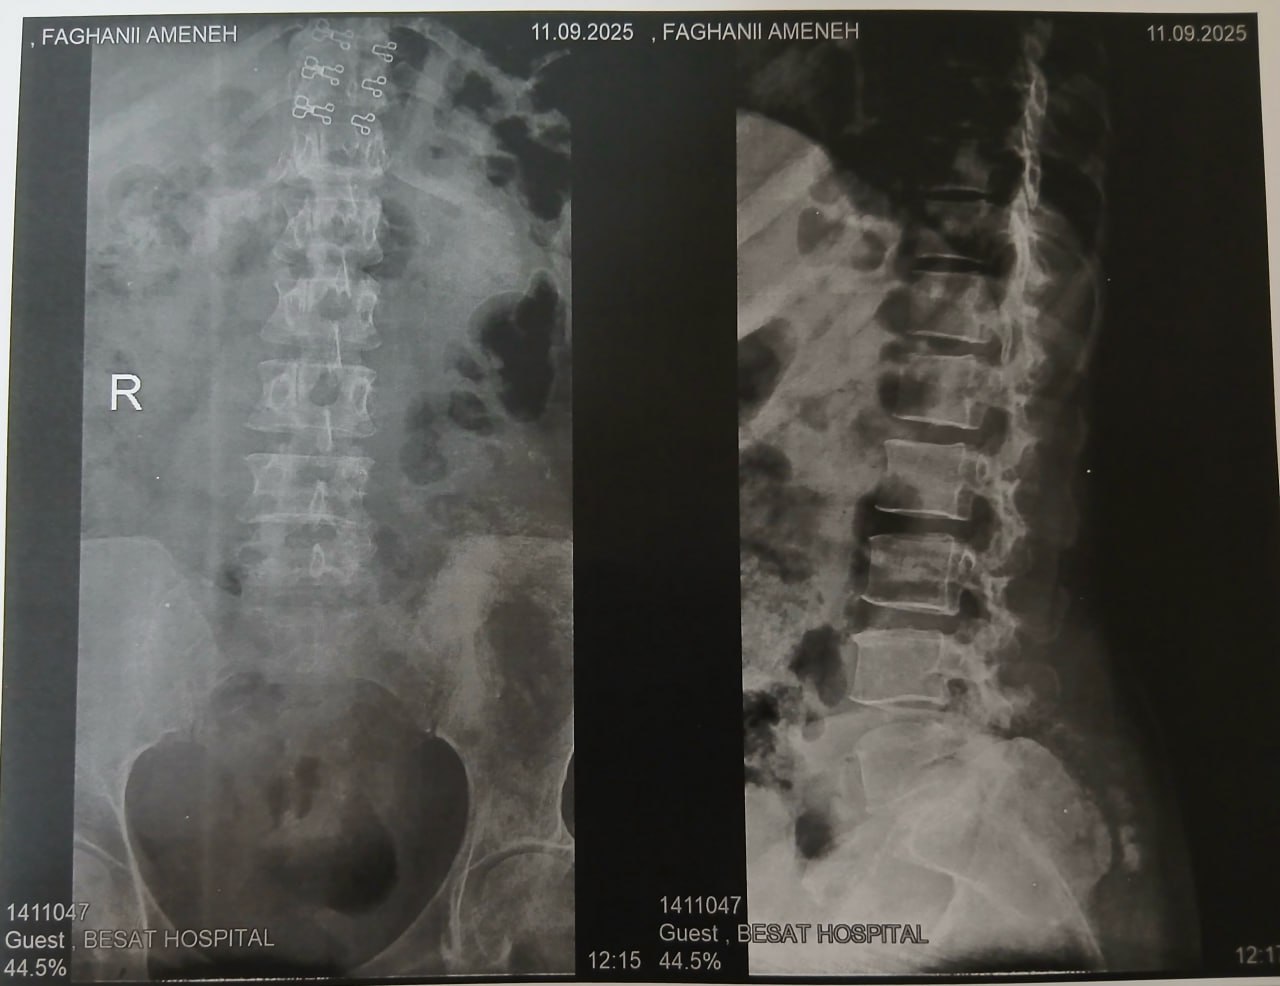

(تصویر مربوط به این مراجعه نیست) Other:

(تصویر مربوط به این مراجعه نیست) Other:

(تصویر مربوط به این مراجعه نیست) Other:

(تصویر مربوط به این مراجعه نیست) Other: